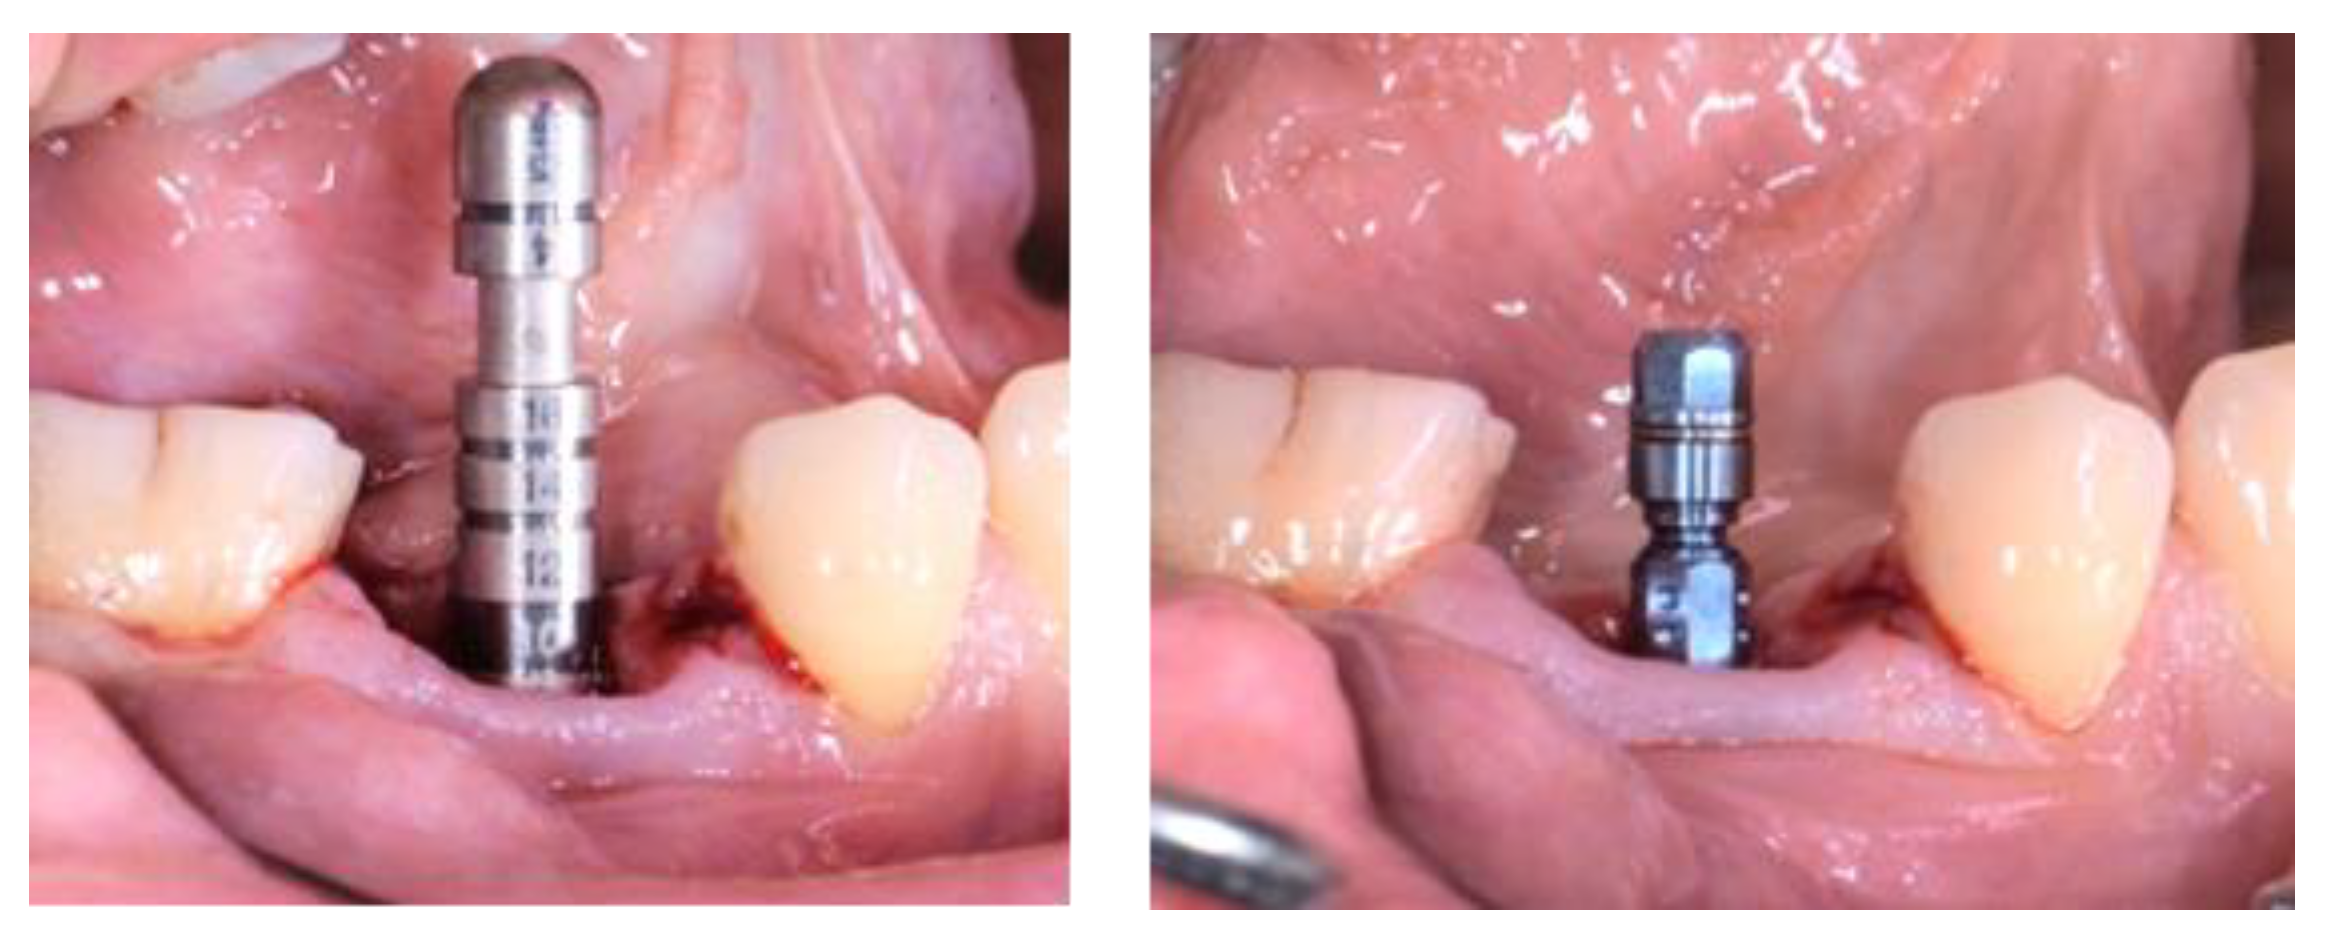

2.3. Treatment Procedure

3.1. Clinical Results